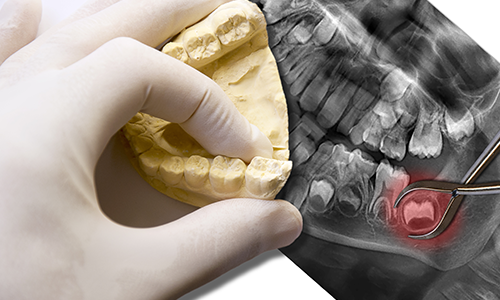

当院では、患者様ご自身の歯に勝るものはないと考えています。一度失った歯は、どんなに優れた人工物でも完全に元通りにすることはできません。そのため、他院で抜歯を勧められたような重度の虫歯であっても、安易に諦めることなく、可能な限り「残す」ための治療を最優先に提案いたします。

親知らずの抜歯に対して「痛い」「腫れる」といった恐怖心をお持ちの方は多いでしょう。当院では、以下の取り組みで患者様の心身の負担を最小限に抑えています。

レントゲン(2次元)では見えない神経の位置や根の形を、3次元画像で正確に把握。余分な切開を避け、スピーディーかつ安全に抜歯します。

真っ直ぐ生えていて、清掃もできており、将来的に活用できる(移植のドナーなど)可能性がある場合は、無理に抜くことはお勧めしません。

痛みが強い時にすぐ抜くと、麻酔が効きにくかったり術後の治りが悪くなったりします。まずは洗浄や投薬で炎症を落ち着かせてから、万全の状態で処置を行います。